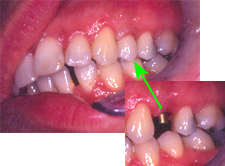

Im Röntgenbild von Abb. 3 ist ein gut erbsengrosses Granulom (Pfeil) an der Wurzelspitze eines toten, devitalen Zahnes feststellbar. Die Patientin wünschte die Erhaltung des Zahnes, zumal auch der vordere Nachbarzahn marktot und beherdet war. Abb. 4 zeigt das Röntgenbild nach der Wurzelfüllung.

Ein halbes Jahr später hat die Patientin sich dazu entschlossen, den vorderen beherdeten Zahn auch endodontisch behandeln zu lassen. An Abb. 5 wird im Röntgenbild die Wurzellänge mit Instrumenten bestimmt. Man gewinnt auch den Eindruck, dass der bereits vor einem halben Jahr wurzelbehandelte Zahn in Abheilung sei.